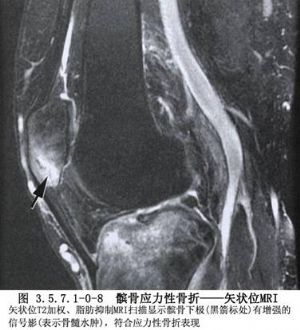

髌骨的解剖及髌骨骨折影像表现见下图(图3.5.7.1-0-1~3.5.7.1-0-10)。